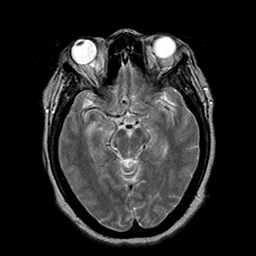

Cerebral hemorrhage, MR Study mr-t2 -- Slice #10